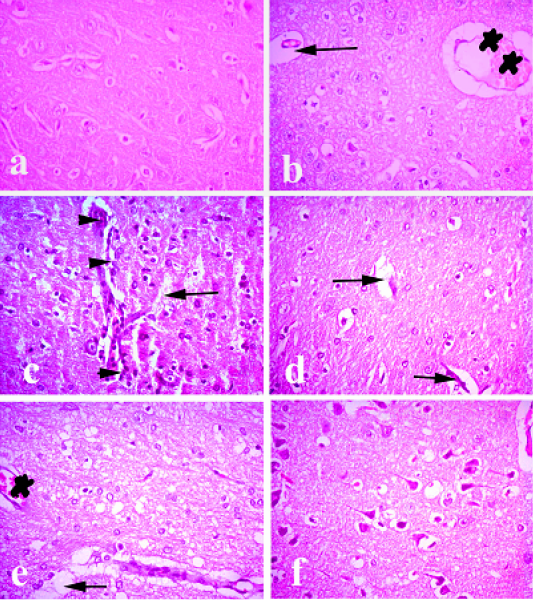

Brain of rabbit. (a) Brain of normal control animals showing normal histological picture. (b and c) Brain of pasteurella infected group showing congestion of blood vessels, lymphocytic infiltrations and degeneration of neurons. (d) Brain treated with ofloxacin showing focal degeneration of some neurons. (e) Brain treated with grape seed extract showing mild congestion and focal degeneration. (f) Brain treated with (O+G) showing fairly normal picture. (arrows) refer degenerated neurons, (arrow heads) refer to lymphocytic infiltration. (stars) refer to congestion. Hematoxylin and eosin stain; magnification, X 100.